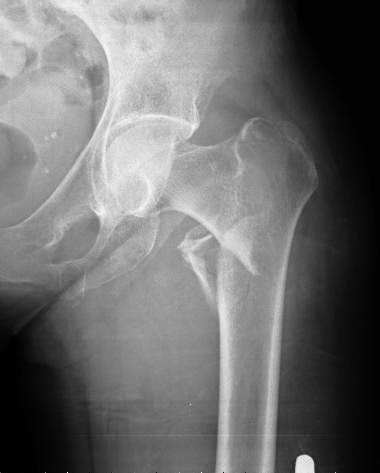

Menopausia precoz y riesgo de fracturas

En un análisis del ensayo Women’s Health Initiative, la menopausia antes de los 40 años se asoció a una mayor frecuencia de fracturas, sin observarse beneficio del reemplazo hormonal o de los suplementos de calcio y vitamina D. Menopause, 31 de octubre de 2016